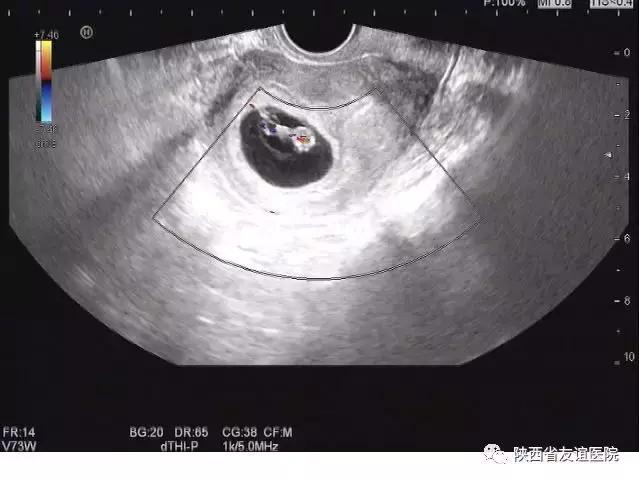

早孕B超图

很多孕妈妈都知道孕期一定要检查的项目就是B超,或者说彩超,而却不明白何为B超?其实B超就是一种超声波检查,与我们平时说话的声波一样,只是因为频率高不被人耳接收,所以听不到,换句话说“超声就是一种听不到的声音”,所以它基本不会对人体产生影响,是一种安全且最常用的影像学检查方式。

然而说它安全也不是绝对的。如果超声波的能量过大,使用时间过长则会导致热效应,长时间的累积可能会对人体产生不良的影响。但是,产生影响的前提是“长时间的累积”。而我们在检查的过程中,医生是不会长时间在同一部位检查的,每一个部位的累积时间远远小于产生热效应影响的时间,而且,产科超声的能量设置也是减半的,所以孕妈妈们根本无需担心B超检查会对胎儿造成伤害了。